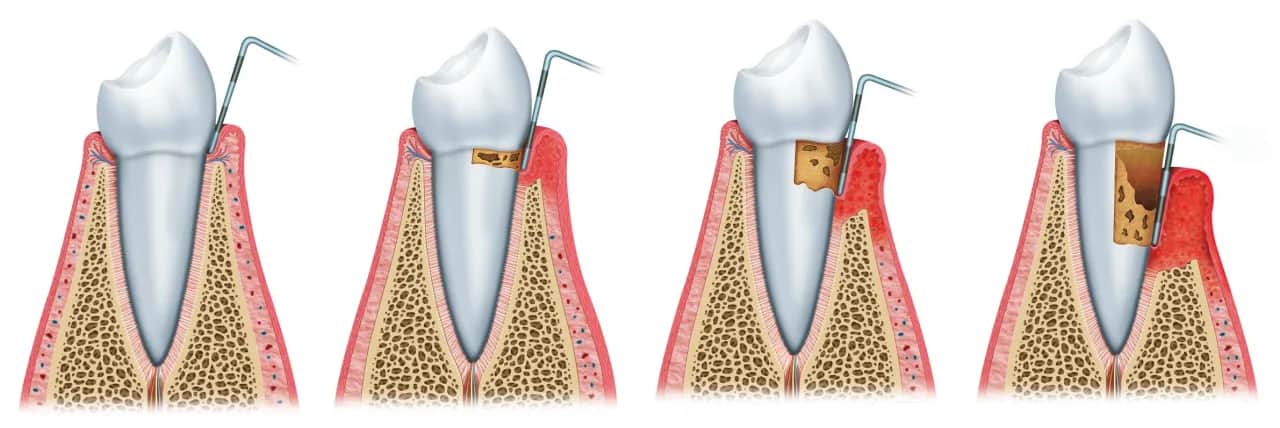

Proces gojenia dziąseł - etapy i ich charakterystyka

Gojenie dziąseł po wyrwaniu zęba to złożony proces, który przebiega w kilku etapach. Po pierwsze, tuż po zabiegu, w zębodole tworzy się skrzeplina, która działa jak naturalny opatrunek. Skrzeplina jest kluczowa, ponieważ chroni ranę przed zanieczyszczeniem i infekcją. W ciągu pierwszych kilku dni, dziąsło może być opuchnięte i zaczerwienione, co jest normalną reakcją organizmu na zabieg.

W miarę upływu czasu, skrzeplina zaczyna się przekształcać w tkankę ziarninową, która jest bardziej zorganizowana i stabilna. Ten etap zazwyczaj trwa od 3 do 7 dni. W ciągu kolejnych dni, tkanka ziarninowa stopniowo łączy się z otaczającymi tkankami, a dziąsło zaczyna się regenerować. Pełne gojenie może zająć od 7 do 10 dni, ale całkowita regeneracja dziąsła może trwać nawet do pół roku, w zależności od indywidualnych czynników zdrowotnych pacjenta.